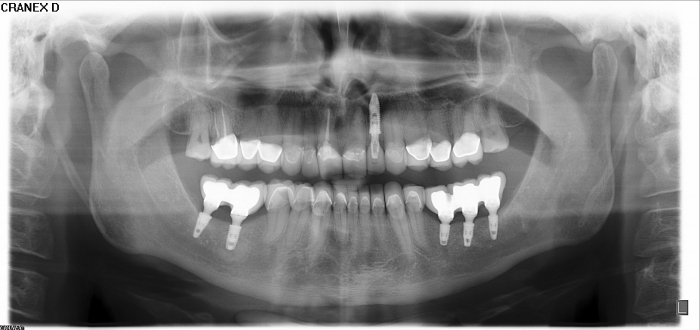

Raio - x Próteses provisórias, em 2015

Próteses Provisórias, em 2015